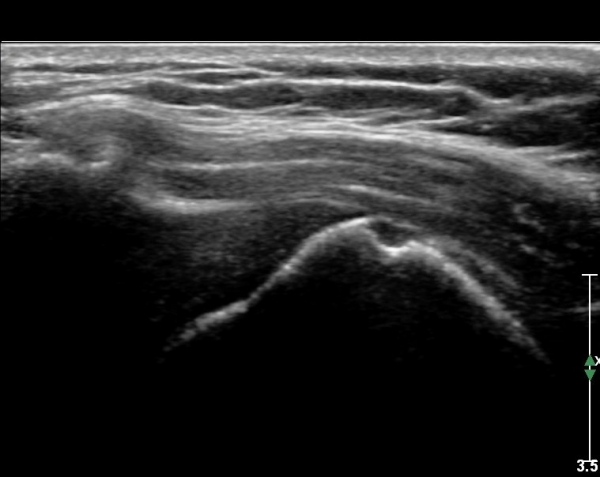

ÃÊÀ½ÆÄ ¼Ò°ß: ¿À±¸µ¹±â¿Í °ßºÀÀ» ¿¬°áÇÏ´Â ¿À±¸µ¹±â°ßº»Àδ밡 Á¤»óÀûÀÎ ¸ð½ÀÀ¸·Î °üÂûµÈ´Ù(»çÁø 1).